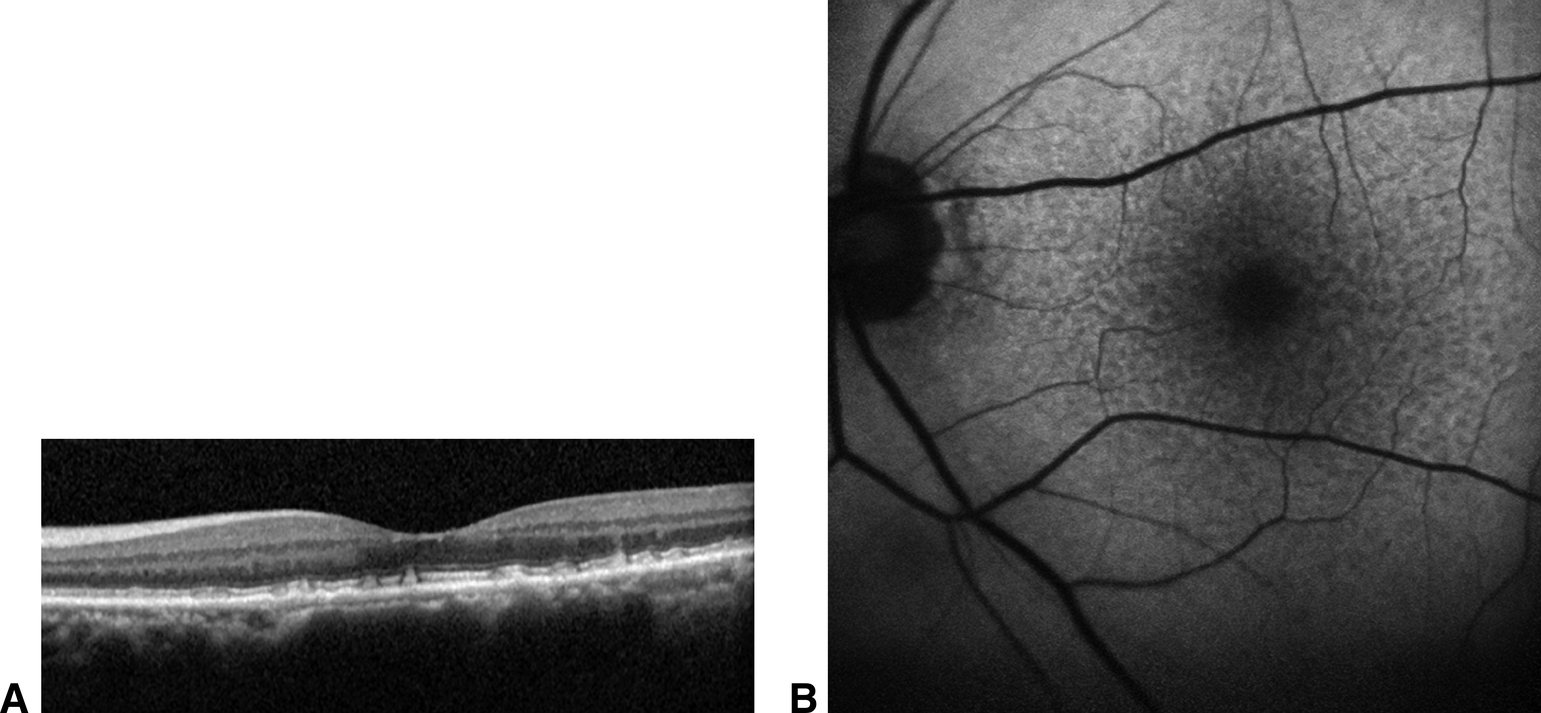

Figure 4-3

A. Image en SD-OCT montrant la localisation des drusen réticulés au-dessus de l'EP. B. Autofluorescence correspondante montrant l'aspect de réseau réticulé de ces drusen.

La technologie spectral domain (SD-OCT) des petits et grands drusen révèle généralement des élévations nodulaires sous l'EP ou même de petits décollements de l'EP avec une absence notable de liquide intrarétinien et sous-rétinien (voir fig. 4-2). Les pseudodrusen réticulés sont identifiés au-dessus de l'EP, mais sous la ligne ellipsoïde et sont classés en fonction de leur épaisseur (voir fig. 4-3).